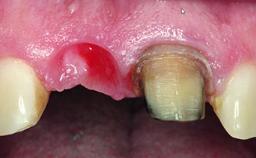

Replacement of an Ankylosed Central Incisor with a Gingival Recession: Tooth Extraction with Socket Grafting and Late Implant Placement with Simultaneous Contour Augmentation

In 2008, a healthy 15-year-old female, non-smoking patient presented at our clinic with a major esthetic problem of tooth 21. Her dental history revealed that the tooth had been avulsed by trauma years before. As a result, the replanted and temporarily splinted tooth had ankylosed and was in severe apical malposition. The ankylosed tooth exhibited a significant gingival recession that disturbed the patient greatly. Due to the patient’s low age and with her skeletal growth not completed, periodic follow-up visits were scheduled to monitor the situation until the patient was old enough for implant therapy.

Soft Tissue Contour and Volume Significantly deficient